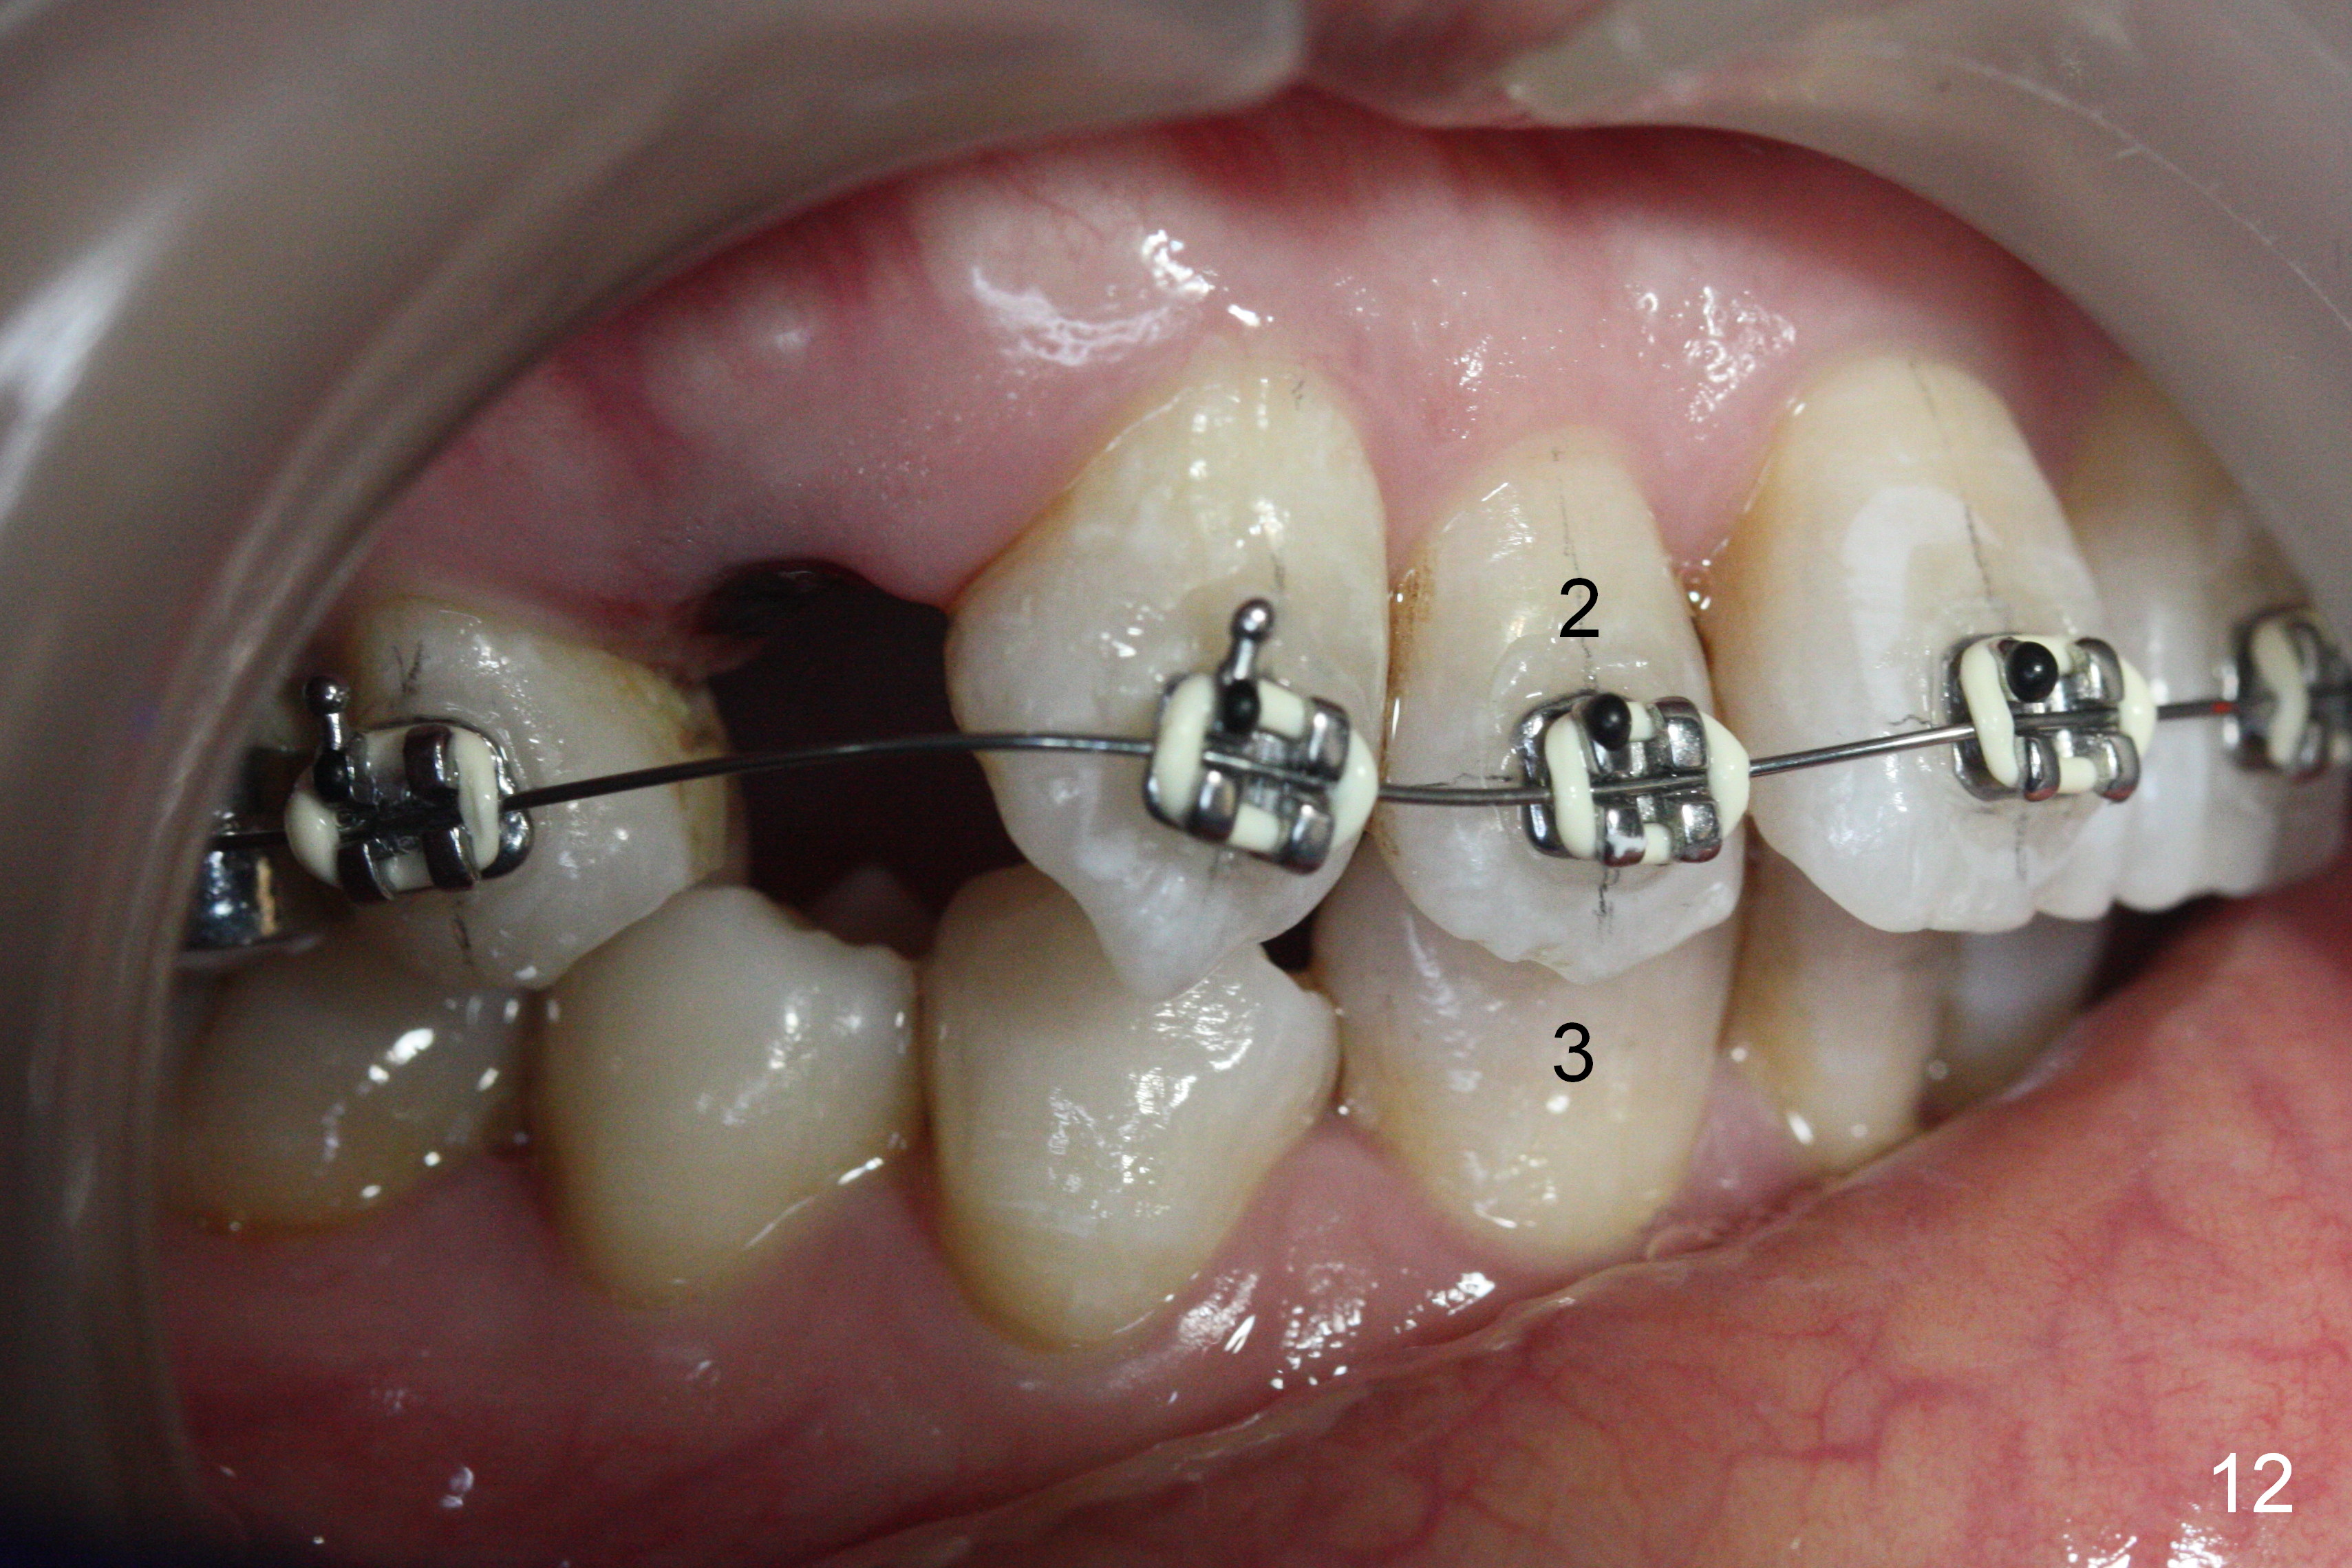

Since U2s are palatally inclined, there is no enough space to place brackets on L3 (Fig.12-14). Lower bracketing is postponed. U4s are extracted 3 days earlier.

Fig.15-17 are taken nearly 2 months post banding. The upper 16 niti is still not fully engaged. Two weeks later, lower brackets are placed with 12 niti wire and occlusal composite (Fig.18-20). Overjet is excessive (Fig.19). Consider distalizing the upper anterior teeth when the upper arch wire changes to a rectangular one.